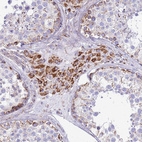

Immunohistochemical staining of human kidney, liver, pancreas and testis using Anti-SUCLG2 antibody HPA046705 (A) shows similar protein distribution across tissues to independent antibody HPA051998 (B).